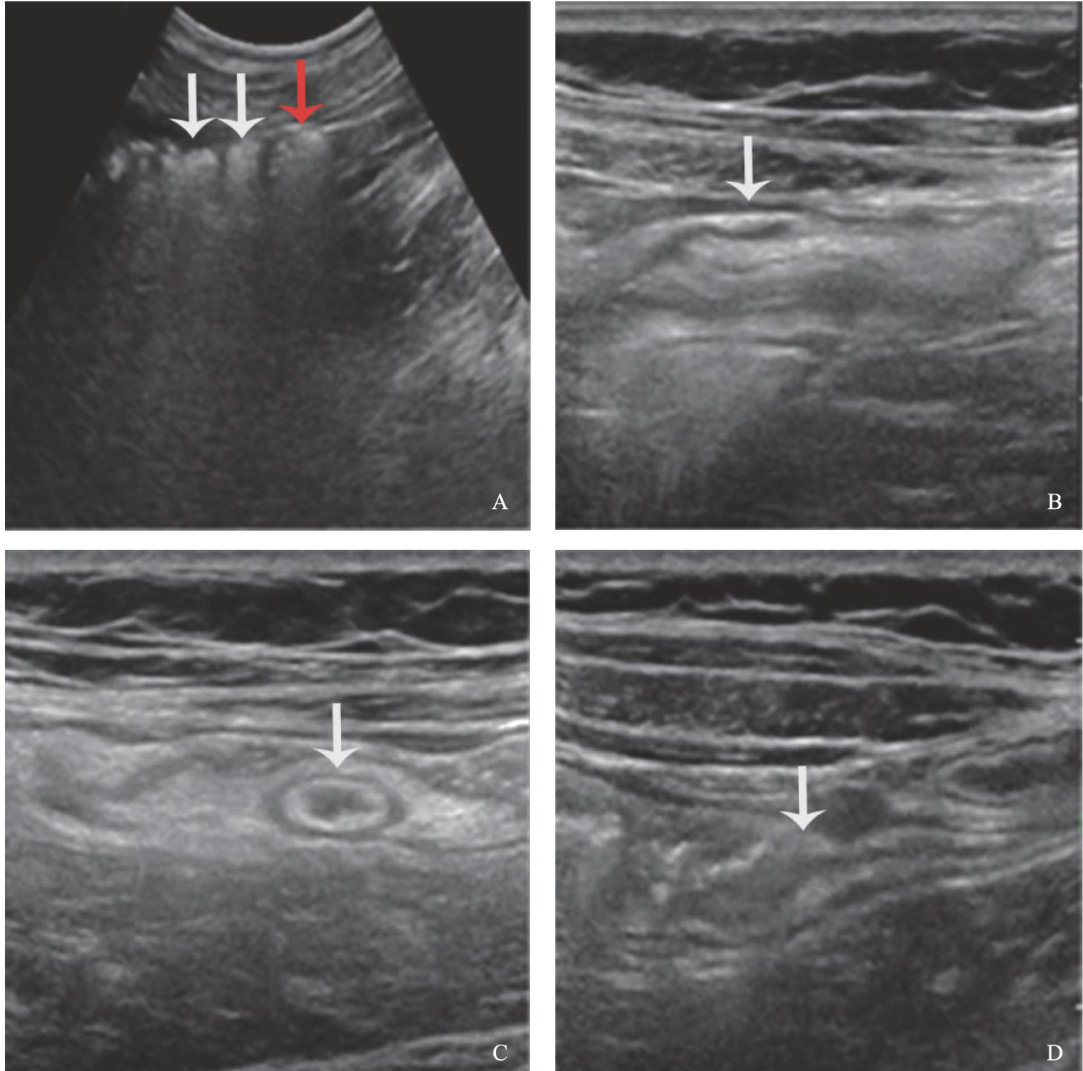

超声对慢性阑尾炎的诊断价值

ABSTRACT: ObjectiveTo evaluate the diagnostic value of ultrasound in chronic appendicitis.MethodsA retrospective analysis was conducted on the ultrasound imaging features of the appendixes in 68 patients with chronicappendicitis(chronic appendicitis group)confirmed bypathological results at the Afiliated Hospital of Inner Mongolia Medical University from January 2023 to December 2O24,as well as 85 healthy volunteers (normal appendix group)of diferent ages with no history of abdominal pain during the same period.Multivariate Logistic regression was employed to investigate the sensitivityand specificity of diffrent variables in diagnosing chronic appendicitis.ResultsThe chronic appendicitis group had higher appendix diameter ( Z=-8.47 , P<0.001 ), unilateral wall thickness ( Z=-7.16 , P<0.001 ),and submucosal thickness( Z=-9.73 , P<0.001 )than the normal appendix group. Appendix diameter ( OR=3.11 , 95%CI=1.37- 7.02, P=0.006 )and submucosal thickness ( OR=5492.73 ,95% CI=89.53-336 984.13, P<0.001 )were identified as independent factors for diagnosing chronic appendicitis,while gender,age,unilateral wall thickness,and intraluminal conditions had no significant impact on the diagnosis of chronic appendicitis(all P>0.05 ). When appendix diameter combined with submucosal thickness was usedasa joint diagnosticindicator,the model demonstrated the bestperformance,with the sensitivity of 92.65% ,the specificity of 97.65% ,and the accuracy increasing to 95.42% : ConclusionThe combined use of appendix diameter and submucosal thickness can significantly improve the accuracy,specificity,and reliability of ultrasound in diagnosing chronic appendicitis.